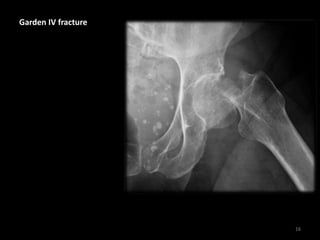

Garden IV fracture

16

• Loss of Shenton's line

• Complete fracture of

the full diameter of

the femoral neck

• Total displacement of

the 2 fracture

components

17